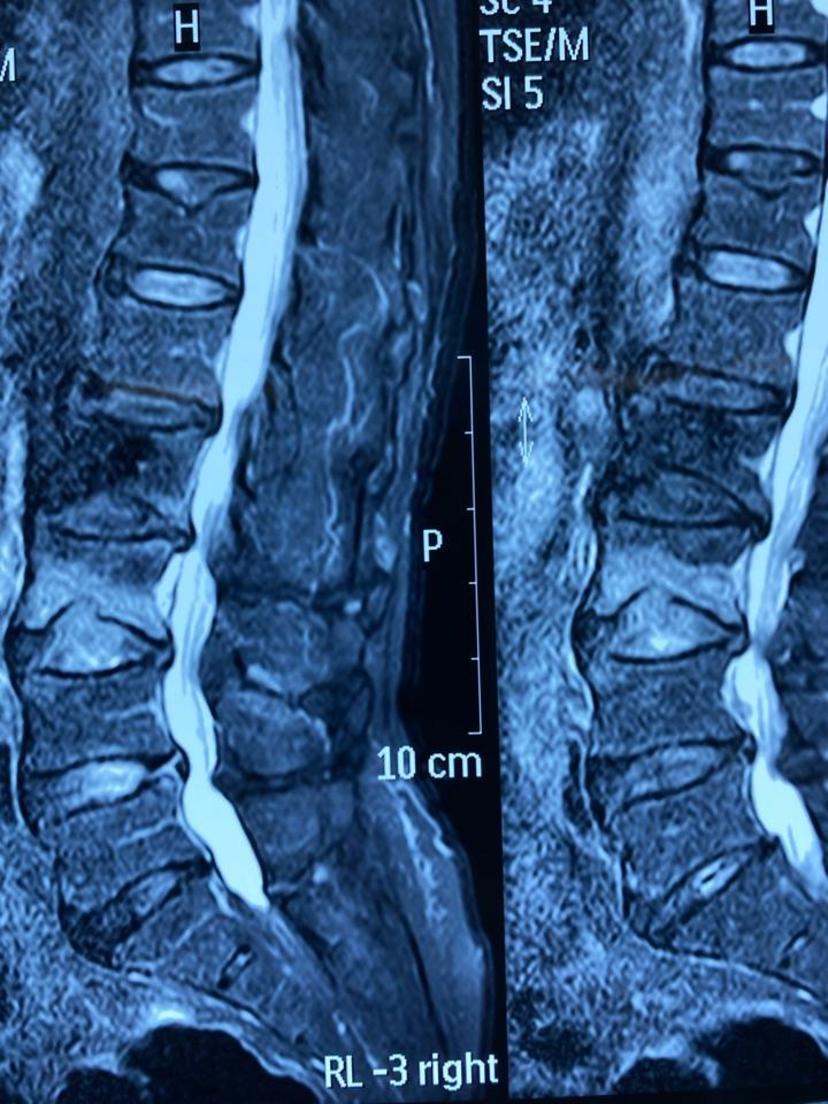

80岁老爷子因骨质疏松几年前腰椎发生过一次骨折,这次无明显外伤史再次感腰背部疼痛难忍、不能站立行走、卧床翻身困难,经腰椎磁共振及骨密度检查(诊断腰3椎体压缩性骨折、骨质疏松症),在局部麻醉、G臂机定位下行骨水泥灌注微创手术治疗,回病房后腰痛症状完全消失、床上翻身自如,术后次日早上康复出院!在此提醒患有骨质疏松的高龄患者,建议正规抗骨质疏松治疗、适当补钙、多晒太阳、适当户外运动,避免弯腰搬重物、谨防摔跤,一旦出现严重腰背痛、影响生活,建议到正规医院就诊。腰椎磁共振显示腰3椎体压缩骨折

磁共振示:腰3骨折、椎体下缘部分缺如